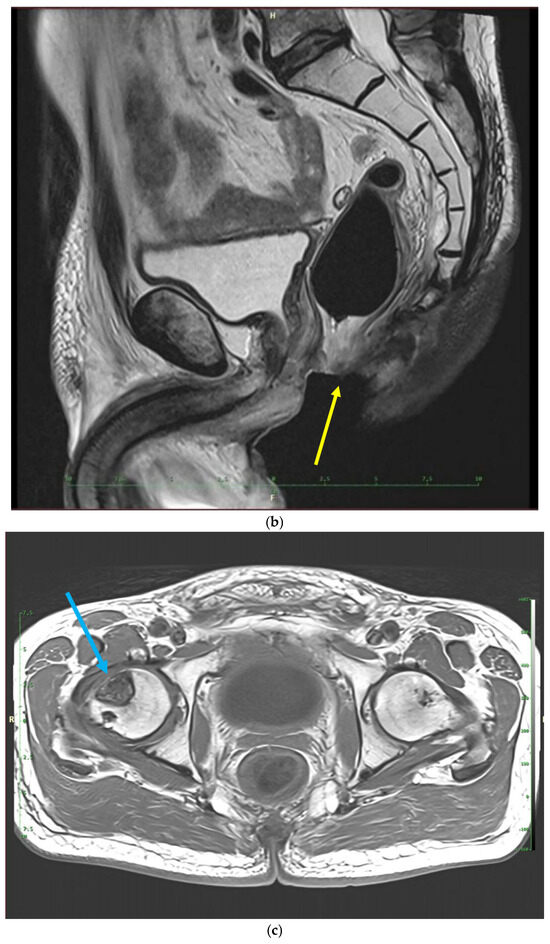

Recently, inflammatory reactions adjacent to the necrosis have slowly progressed to the lower arm of the left pubic and ischium bone and have induced mild osteomyelitis demanding antibiotic and analgesic treatment (Figure 2 and Figure 3). The osteonecrotic focus within the right femoral head and acetabulum is now stable, asymptomatic, and painless.

Figure 3.

MRI scans 26 years after radiotherapy: T1-weighted axial MRI scan shows vast perineal and anal defects progressing to the left lower arm of the pubis with signs of induced osteomyelitis (orange arrow) (a); T2-weighted sagittal scan shows vast perineal and anal defects including absence of anal sphincter (yellow arrow) (b); and T1-tse weighted axial scans show the osteoradionecrosis of the right hip (blue arrow) (c).